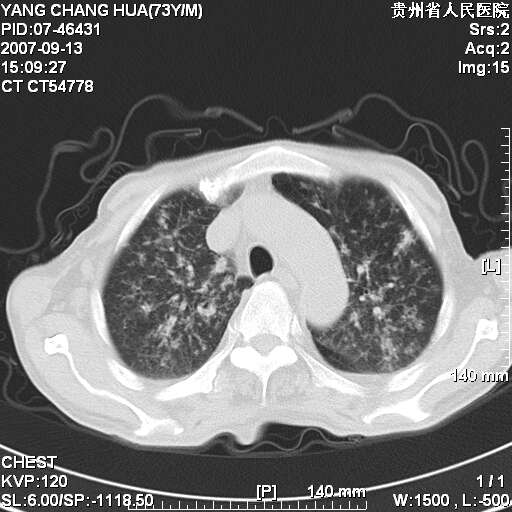

图像没有传全。肺部为感染性病灶;肺囊肿;双侧胸腔积液;肝脾肿大;腹水。

双肺部为感染性病灶.双侧胸腔积液;肝脾肿大;腹水.

双肺部为感染性病灶.双侧胸腔积液;肝脾肿大;脾脏密度不均,不除外脾侵润?腹水.

恶性淋巴瘤,双肺部也是.

双肺部为感染性病灶.双侧胸腔积液;肝脾肿大;腹水

图片不全.就这几张图片.无法诊断淋巴瘤的,我考虑:双肺部为炎性病灶.双侧胸腔积液;肝脾肿大;腹水

双肺点片状影,以双上肺改变明显.双侧胸腔积液.为感染性病灶,但不除外结核.

双上肺继发型肺结核。

双肺散在斑片状及多发小结节状阴影,边缘模糊,双上肺野明显,双侧胸膜腔少量积液,纵隔及肺门区未见明显肿大淋巴结,肝脾肿大,脾内见多发低密度区,结合临床考虑恶性淋巴瘤(肺内表现为肺炎肺泡型),单看影像表现,肺结核不能排除。建议结合实验室检查或表浅淋巴结活检。

肺部为;恶性淋巴瘤;双侧胸腔积液;肝脾肿大;腹水。